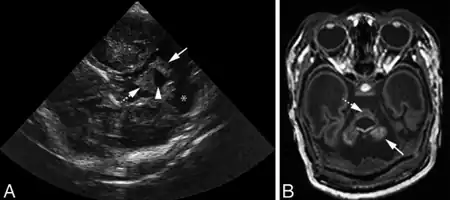

- ↑ Steggerda, S. J.; de Bruïne, F. T.; Smits-Wintjens, V. E. H. J.; Verbon, P.; Walther, F. J.; van Wezel-Meijler, G. (September 2015). "Posterior fossa abnormalities in high-risk term infants: comparison of ultrasound and MRI". European Radiology. 25 (9): 2575–2583. doi:10.1007/s00330-015-3665-8. ISSN 1432-1084. Retrieved 18 July 2023.